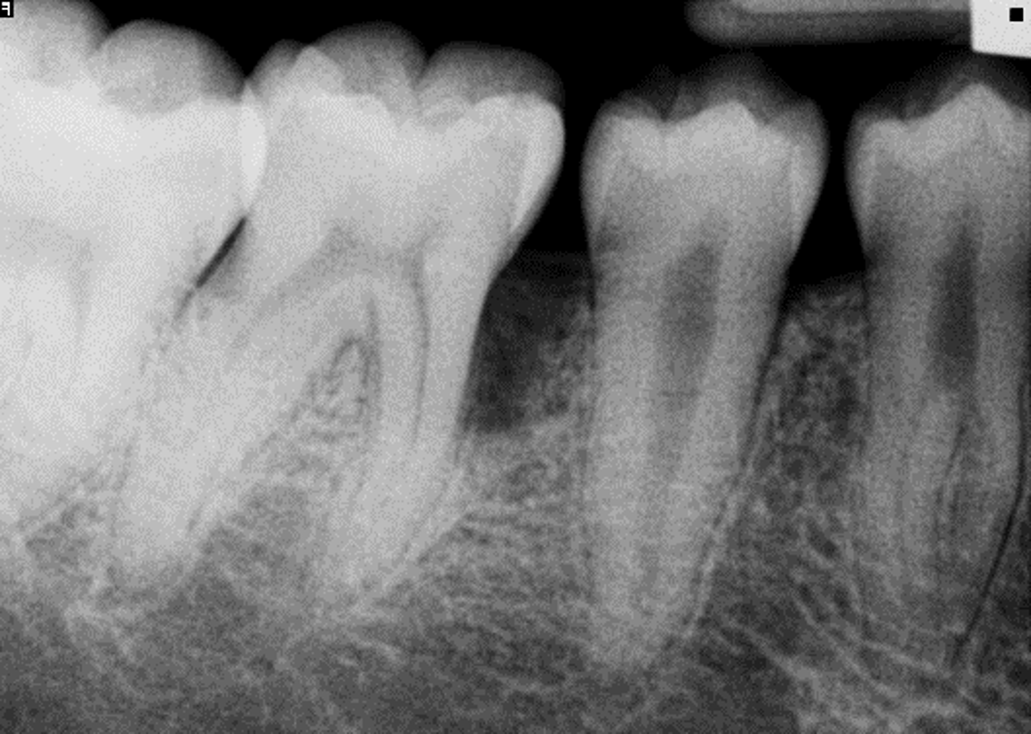

Tooth #30

Challenge: Patient presented with a severe intrabony defect (>50% bone loss) on the distal of #30, threatening tooth retention.

Solution: Minimally invasive regenerative therapy utilizing bone graft and barrier membrane to rebuild attachment.

Outcome: 100% bone regeneration achieved with complete papilla preservation. Patient reported zero post-operative pain.